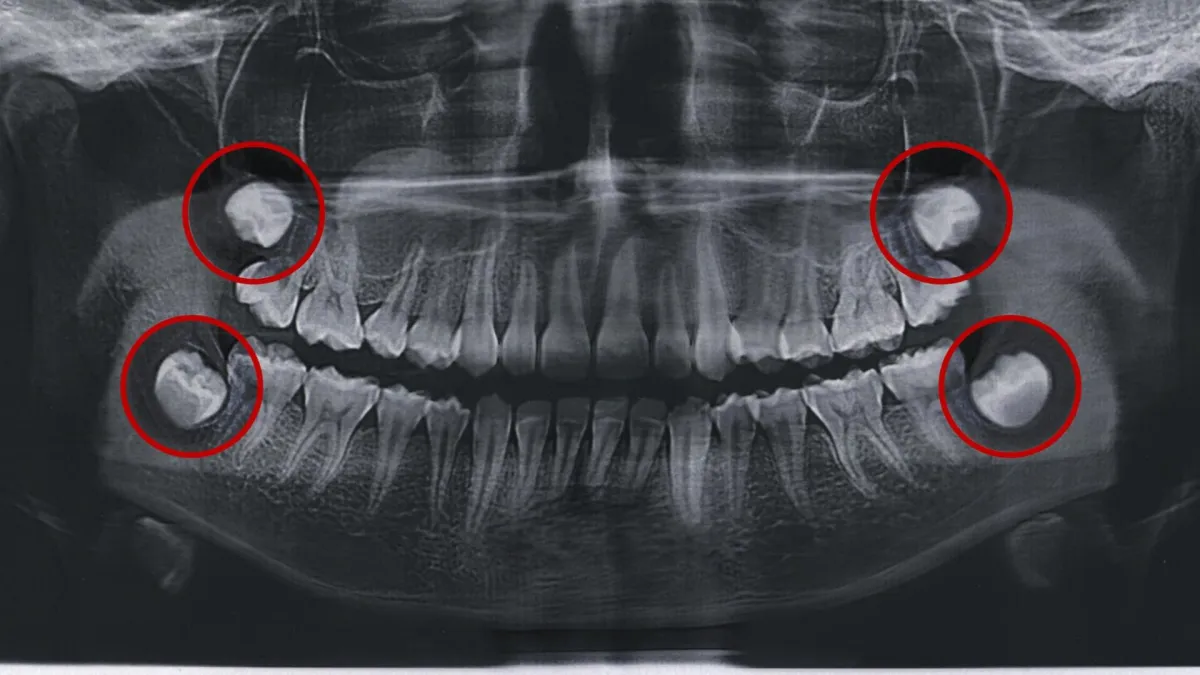

Wisdom teeth are notoriously painful. They seem to come whenever they please, and when they do, they can easily wreak havoc. Pericoronitis is an infection that can occur when your wisdom teeth don’t come in properly. The risk of this spreading is too high to neglect.

If you get it, you’ll know because of your irritated gums in that area, as well as possible bad breath. You'll likely feel a painful pressure in your wisdom teeth area also. See a dentist as soon as possible to get this resolved.

Growing wisdom teeth can be painful and may result in pericoronitis, an infection that can spread if left untreated. If your gums in the wisdom tooth area are inflamed, and you have bad breath, it could be a sign of pericoronitis caused by the infection. You may also experience painful pressure in the wisdom teeth area. Contact our office and make an appointment to see us as soon as possible to address the issue and obtain relief from the discomfort.